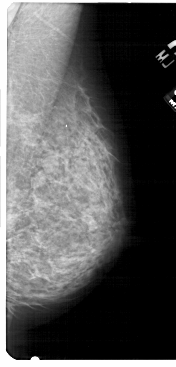

A_1755_1.LEFT_MLO

LEFT_MLO LINES 5491 PIXELS_PER_LINE 2671 BITS_PER_PIXEL 12 RESOLUTION 43.5 OVERLAY